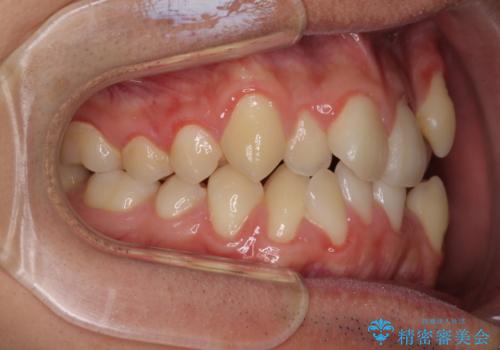

- 上下の八重歯や乱杭歯を気にして来院され患者様です。

スペースを確保するため、上下左右の小臼歯を抜歯し、ワイヤー装置に矯正することとしました。

奥歯の咬み合わせの左右差が大きかったため、変則的な抜歯矯正を行いました。

治療期間はやや長期化しましたが、満足のいく歯並びとなりました。